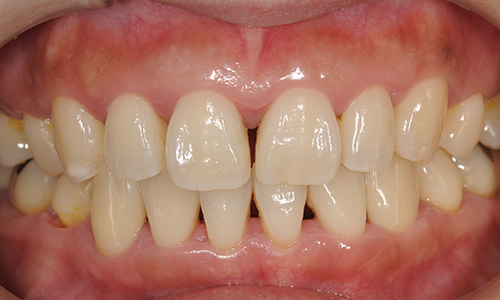

レントゲン写真の歯槽骨の頂点に線を引いていますが、線は波をうったような状態になっています。写真の口腔内では炎症は部分的に認められます。そして全体的に歯肉が下がり、「すきま」ができています。歯根が少し見えてくるため、歯が長くなったような状態になっています。